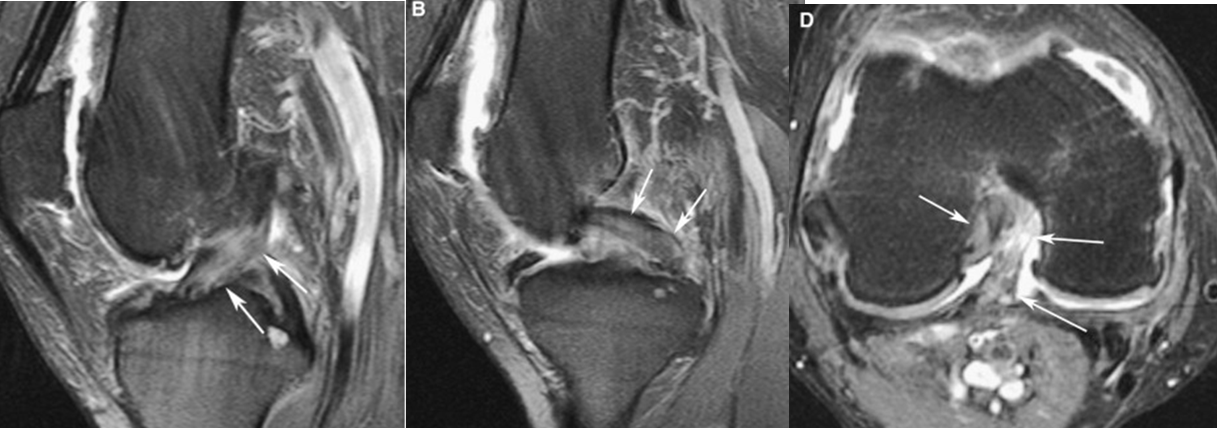

Q. ¿PRINCIPALES HALLAZGOS DE ESTAS IMÁGENES Y A QUE GRADO INESTABILIDAD ROTATORIA POSTEROLATERAL (PLRI) CORRESPONDE ?

Inestabilidad rotatoria posterolateral, grado 1. Resonancia magnética ponderada por PD del FS coronal que muestra una avulsión de la colateral del ligamento cubital lateral proximal y retracción del fragmento óseo (flechas blancas). El edema de la médula ósea se observa en el capitelo (puntas de flecha blancas) y la cabeza radial (asteriscos blancos).